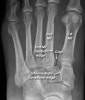

양측 체중부하 상태, 체중부하하지 않은 상태에서 족부 정면 X-ray 사진을 찍습니다.

제 1, 2 중족골 기저부의 간격이 건측에 비해 크고 체중부하 상태에서의 해당 간극의 변화가 건측에 비해 큽니다.

내측, 중간 설상골 사이가 벌어져 있으며, 설상골간인대도 파열되어 있습니다.

X-ray : Lisfranc 인대 손상 (Lisfranc injury, Midfoot sprain)